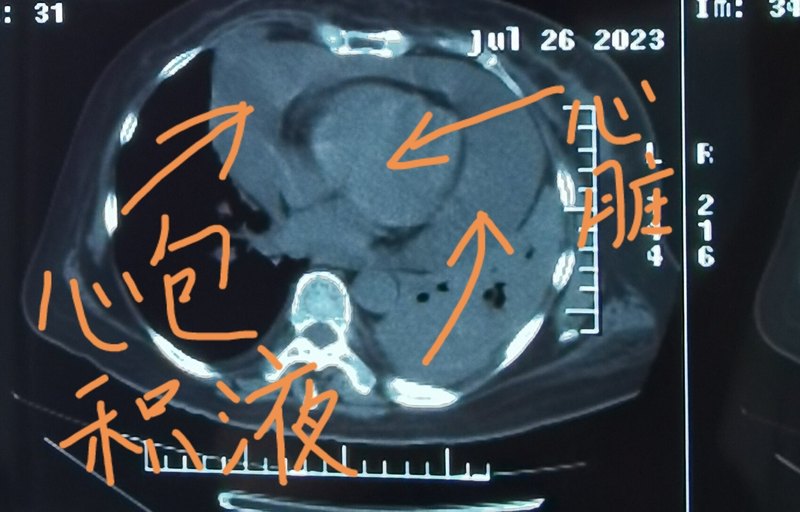

劉懿博士說肺癌(六一九四)肺癌引起大量心包積液,病情嚴重么?

有一位晚期肺癌的患者,最近覺得憋氣比較嚴重,并且雙下肢出現(xiàn)了水腫,復查完胸部CT,家屬帶著片子過來找我看。從CT片中可以看到這位患者出現(xiàn)了大量的心包積液,心包積液的深度已經(jīng)超過三厘米。家屬問,這種情況是不是說明病情比較嚴重了?確實是這樣,有些肺癌患者到了晚期,就會侵犯心包,引起心包積液,一般認為深度超過兩厘米,就屬于大量心包積液。大量的心包積液會擠壓心臟,讓心臟跳動沒有那么用力,引起全身的水腫,其中就包括雙下肢水腫,這種情況還是比較嚴重和危險的。這時一方面需要進行心包穿刺引流,把心包積液引出來緩解患者的癥狀,另一方面要進行針對肺癌的系統(tǒng)治療,如果治療沒有效果,心包積液還會再次產(chǎn)生,這時,患者的生存期就不會太長了,家屬也要做好心理準備。